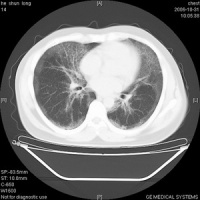

本组共6例经病理学证实为pap患者,其多层ct诊断结果分别为:特发性肺间质纤维化2例;浸润型肺结核1例;肺泡癌1例;肺炎1例;肺泡蛋白沉积症1 例,诊断正确率17%。6例患者均见双肺散在分布的毛玻璃样高密度影,密度欠均匀,形态呈三角形、方形和多边形,少数呈圆形、弧形或线形,全部病灶边界清楚。其中4例可见部分病灶融合呈片块状。所有患者病变分布以肺门区及肺野外带为主,上下肺叶均可见到,在周围正常肺组织衬托下。4例患者的hrct图像还可见到在斑片状毛玻璃影中增多、增粗、紊乱的肺小叶间隔,呈铺路石样(crazy paving appearance)表现[4'5],见图2。病变与周围肺组织分界清楚,相邻肺组织未见明显异常表现。本组所有病例未见支气管气像,msct增强扫描均未见病灶强化以及纵隔肺门淋巴结肿大征象。心脏大小形态在正常范围。

肺泡蛋白沉积症临床非常罕见,由rosen等[6]于1958年首先报道,其病因及发病机制至今仍不清楚, 目前认为与肺泡表面物质代谢异常或肺泡巨噬细胞的清除异常有关,部分患者还可能与粉尘或某些化学物质吸入所致的特异性反应有关,也可能与自身免疫机制障碍、血液淋巴系恶性肿瘤以及细胞毒性药物的应用有关3.1 影像与病 理学 联系 肺泡腔内充满大量粉红色云絮状或细颗粒状无定形蛋白质样物质为pap的主要病理改变,而肺泡壁、支气管壁和胸膜病变不明显。病变区与相邻正常肺组织界限清楚,肺泡结构保持完整,肺泡间隔多数正常,少数可因间隔水肿及淋巴细胞浸润而增厚[8]。病变 发展的不同阶段,肺泡蛋白沉积症出现不同的影像学征象。当病变仅累及肺泡腔,以蛋白质样物质充填肺泡腔为主,而肺泡间隔无水肿及炎症细胞渗出时,ct检查可见肺野内毛玻璃样斑片状高密度影,病变与周围正常肺组织形成明显分界,在肺野中呈地址样表现[2'3]。本组所有患者均可见此征象。其形成机制尚不明确,可能与病变分布以肺小叶为单位,小叶间隔在一定程度上限制了病变蔓延有关。根据 文献,即使做过肺灌洗的患者,其剩余的肺实变仍然边界清楚[5]。msct增强扫描病灶未见强化,说明病灶缺乏血供及无肉芽组织形成。当病变累及小叶间隔,小叶间隔因水肿及炎症细胞浸润而增厚时,hrct上可见实变区出现增厚的小叶间隔,围绕实变的肺小叶形成铺路石样表现,具有一定的特征性[4'5]。本组4 例患者见此征象。hrct能够清楚地显示pap患者的次级肺小叶结构,发现胸部x线平片及常规ct所不能发现的pap患者肺小叶及小叶间隔病变,从而更好地评定病变范围及严重程度,具有重要价值。本组中hrct图像显示pap患者增粗的肺纹理符合小叶间隔走行,与肺部纤维化表现不同,病理学上pap患者的小叶间隔也无纤维化改变发生。pap病变分布以双肺多见,可仅累及一侧[9],肺野中央及外周均可发生,上下肺分布无明显差异[3'9'10]。文献报道当实变肺泡与含气肺泡混杂并存时,还可见到实变阴影内出现蜂窝状透光区,但是支气管气像不多见[9]。本组病例中均未见。肺泡蛋白沉积症为非感染病变,部分学者认为该病不伴有纵隔、肺门淋巴结肿大,若出现明显淋巴结肿大则多数与感染有关[11]。本组所有病例均未见到纵隔、肺门淋巴结肿大。

总之,对于肺部弥漫性病变,ct表现为地址样及铺路石样时,高度提示pap诊断。胸部ct扫描特别是hrct能提高对pap的早期正确诊断。[4'7'8]。本病好发于30~50岁成人,偶见于儿童及老年患者,男性多于女性。多数患者起病隐袭,临床表现无特征性,常见症状为活动后气促、咳嗽、咳少量白色黏液痰,亦可为干咳无痰。低热、乏力、胸痛、咯血者少见,部分病例可咯出小块胶冻样物质。部分患者体格检查可闻及少许肺底部湿啰音,约1/5患者出现杵状指,重者可致发绀。患者预后差异大,部分可自行缓解,复发常见,约1/3患者因呼吸衰竭或合并感染而死亡。